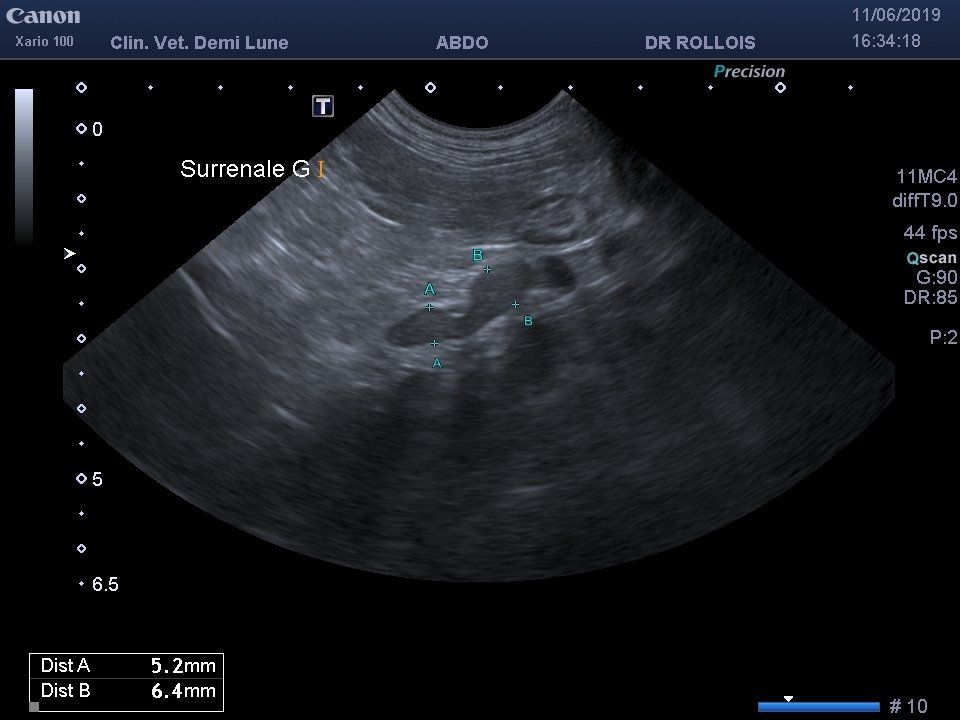

Le principe de l’échographie est d’envoyer des ultrasons qui sont plus ou moins réfléchis par les organes traversés. La sonde qui envoie les ultrasons les réceptionne et construit une image en fonction de leur intensité.

Cet examen est réalisé le plus souvent en votre présence et permet d’examiner les organes abdominaux (échographie abdominale), ou le cœur en activité (échocardiographie). L’échographe de la clinique vétérinaire demi-lune est récent et possède 3 sondes : une sonde pour l’examen des organes abdominaux et 2 sondes spécialisées dans l’examen cardiaque.

L’échographie abdominale est indiquée pour l’exploration des maladies des reins, de la rate, du foie mais aussi pour les diagnostics de gestation (visualisation des fœtus et des battements cardiaques), pour l’exploration du tube digestif et de certaines maladies hormonales.

En cas d’anomalie, certains prélèvements peuvent aussi être réalisés sous échographie : prélèvement urinaire (cystocentèse), prélèvements à l’aiguille fine, biopsies…